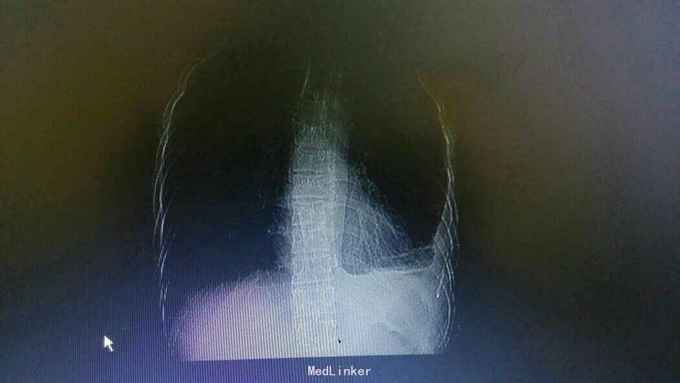

主诉:发热,胸痛10天。 病史:患者10天前无明显诱因出现发热是,伴有乏力,左侧季肋处隐痛,7天前开始出现呼吸困难,平卧时较明显。

查体:左肺呼吸音低,余无特殊。 辅查:胸片提示左侧胸腔积液。

诊断:结核性胸膜炎 治疗:入院予以左侧胸水引流,T-SPORT A68,B24。予以四联抗结核治疗。辅查胸部CT患者左侧胸水减少,病情好转。